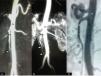

A computed tomography (CT) scan showed occlusion of the superior mesenteric artery (SMA); the other arteries were normal (Figure 1A).

(A) A computed tomography (CT) scan within the first 24hours showed absence of contrast in the superior mesenteric artery (SMA) (arrow). Follow-up CT scans demonstrated gradual improvement in flow through the SMA (arrows) at 10 days (B) and two months (C). Ao: aorta; SMA: superior mesenteric artery.

As periodic CT scans showed progressive improvement of blood flow through the SMA, the patient continued therapy with acenocoumarol (Figure 1B and C).